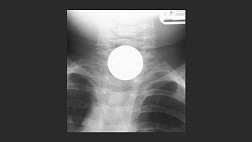

63-летний мужчина с отдаленным анамнезом множественных эзофагеальных дилатаций, вторичных по отношению к рецидивирующим стриктурам, обратился с большой, 6-сантиметровой перфорацией среднегрудного отдела пищевода после употребления колбасы. Ему была проведена правая торакотомия с попыткой восстановления дефекта с помощью мышечного лоскута; однако утечка сохранялась. Затем пациенту было установлено несколько пищеводных стентов и наложено пищеводное шовное покрытие, при этом утечка сохранялась. Затем был установлен CSO, и было отмечено значительное улучшение. Исследование с глотанием бария через 2 месяца показало продолжающееся разрешение его пищеводной утечки, и он не сообщал о какой-либо дальнейшей утечке ( рис. 3 ).

Рисунок 3. Исследование с глотком бария, показывающее полное разрешение пищеводного свища после установки CSO. Устройство CSO показано желтой стрелкой . CSO , установка окклюдера перегородки сердца.